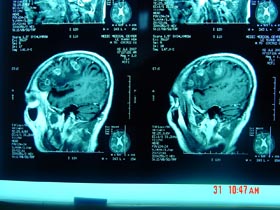

- Đặc biệt chụp cắt lớp vi tính ở não cho thấy có 6 ổ khối u nhỏ ở 2 bên bán cầu não, kích thước nhỏ 20mm, khối u tròn, không có chân, bên trong có hoại tử trắng đều trên film.

+ Chụp cắt lớp vi tính ở não:

·Các khối u đã thoái triển chỉ còn lại 1-2 khối u nhỏ, kích thước 10-15mm, bên trong đã hoại tử trắng, không có chân, không có phù nề xung quanh khối u.

·Không có hình ảnh bất thường ở 2 bán cầu não.

| Hình 2. Hình ảnh chụp vi tính cắt lớp não trước khi điều trị |